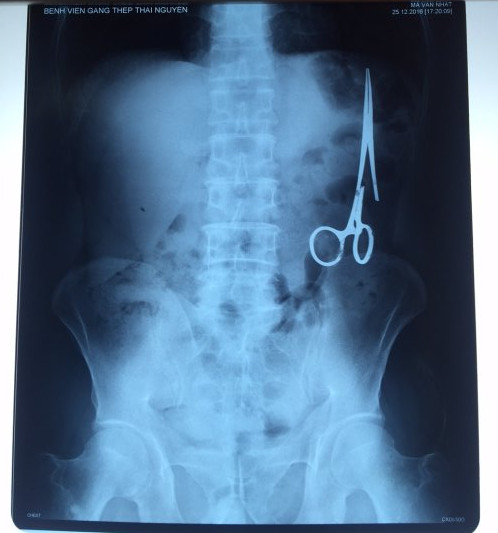

遺留在病人腹中的剪刀

據越南青年報1月2日報道,在越南首都河內醫(yī)療專家的幫助下,越南東北部的太原?。═hai Nguyen)鑄鋼醫(yī)院的醫(yī)生日前從54歲患者M.V.N腹中取出一把醫(yī)用剪刀。這把剪刀是此前曾為M.V.N手術的醫(yī)生遺留的,已經在其腹中待了18年時間。

醫(yī)務人員表示,這把剪刀遺留在病人腹部左側,與結腸緊挨著。剪刀的把手已經生銹,部分器官也已經與剪刀粘連起來。但在過去多年中,M.V.N沒有任何不適感覺,也從未因為留在腹中的剪刀引發(fā)的相關問題去看過醫(yī)生。直到2016年12月,M.V.N因為遭遇了一場車禍,才到鑄鋼醫(yī)院進行身體檢查。

超聲波檢查顯示,M.V.N的腸子中有個奇怪物體,看起來就像醫(yī)用剪刀。M.V.N證實,他曾于1998年6月份在北江省綜合醫(yī)院接受手術,在此后也從未進行過任何手術。近來,他感到腹部有些疼痛,并試圖通過服用藥物治療。12月27日,M.V.N回到北江省綜合醫(yī)院再次進行超聲波檢查,顯示其腹部的確存在怪異物體。